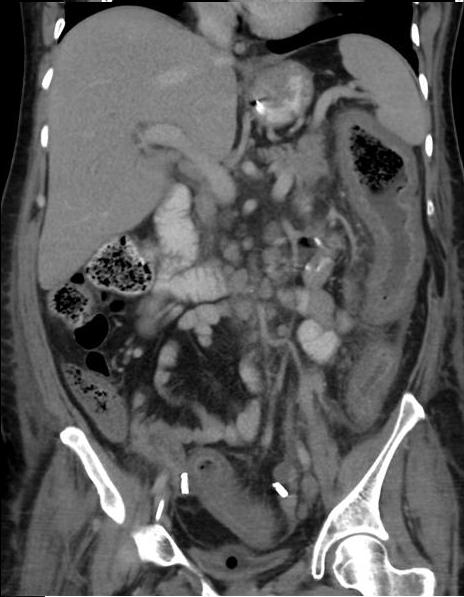

Aspect radiologique TDM

d'une colite pseudomenbraneuse est image de : epaississement

du paroi du colon , image de accordeon " accordion sign " ,

aspect en scie de la muqueuse du colon , peritoineal ascites

tres frequement dans 40% des cas .

Colite pseudomembraneuse :

Epaisissement de la paroie et des haustrals du colon

ascendant et descendant se forment en aspect

empreinte de pouce au bord du colon . Image

radiologique TDM en coupe coronale |

Epaisissement de la paroi du

colon descendant avec aspect en scie de la muqueuse

du colon . Image radiologique TDM du colon en coupe

coronale . |